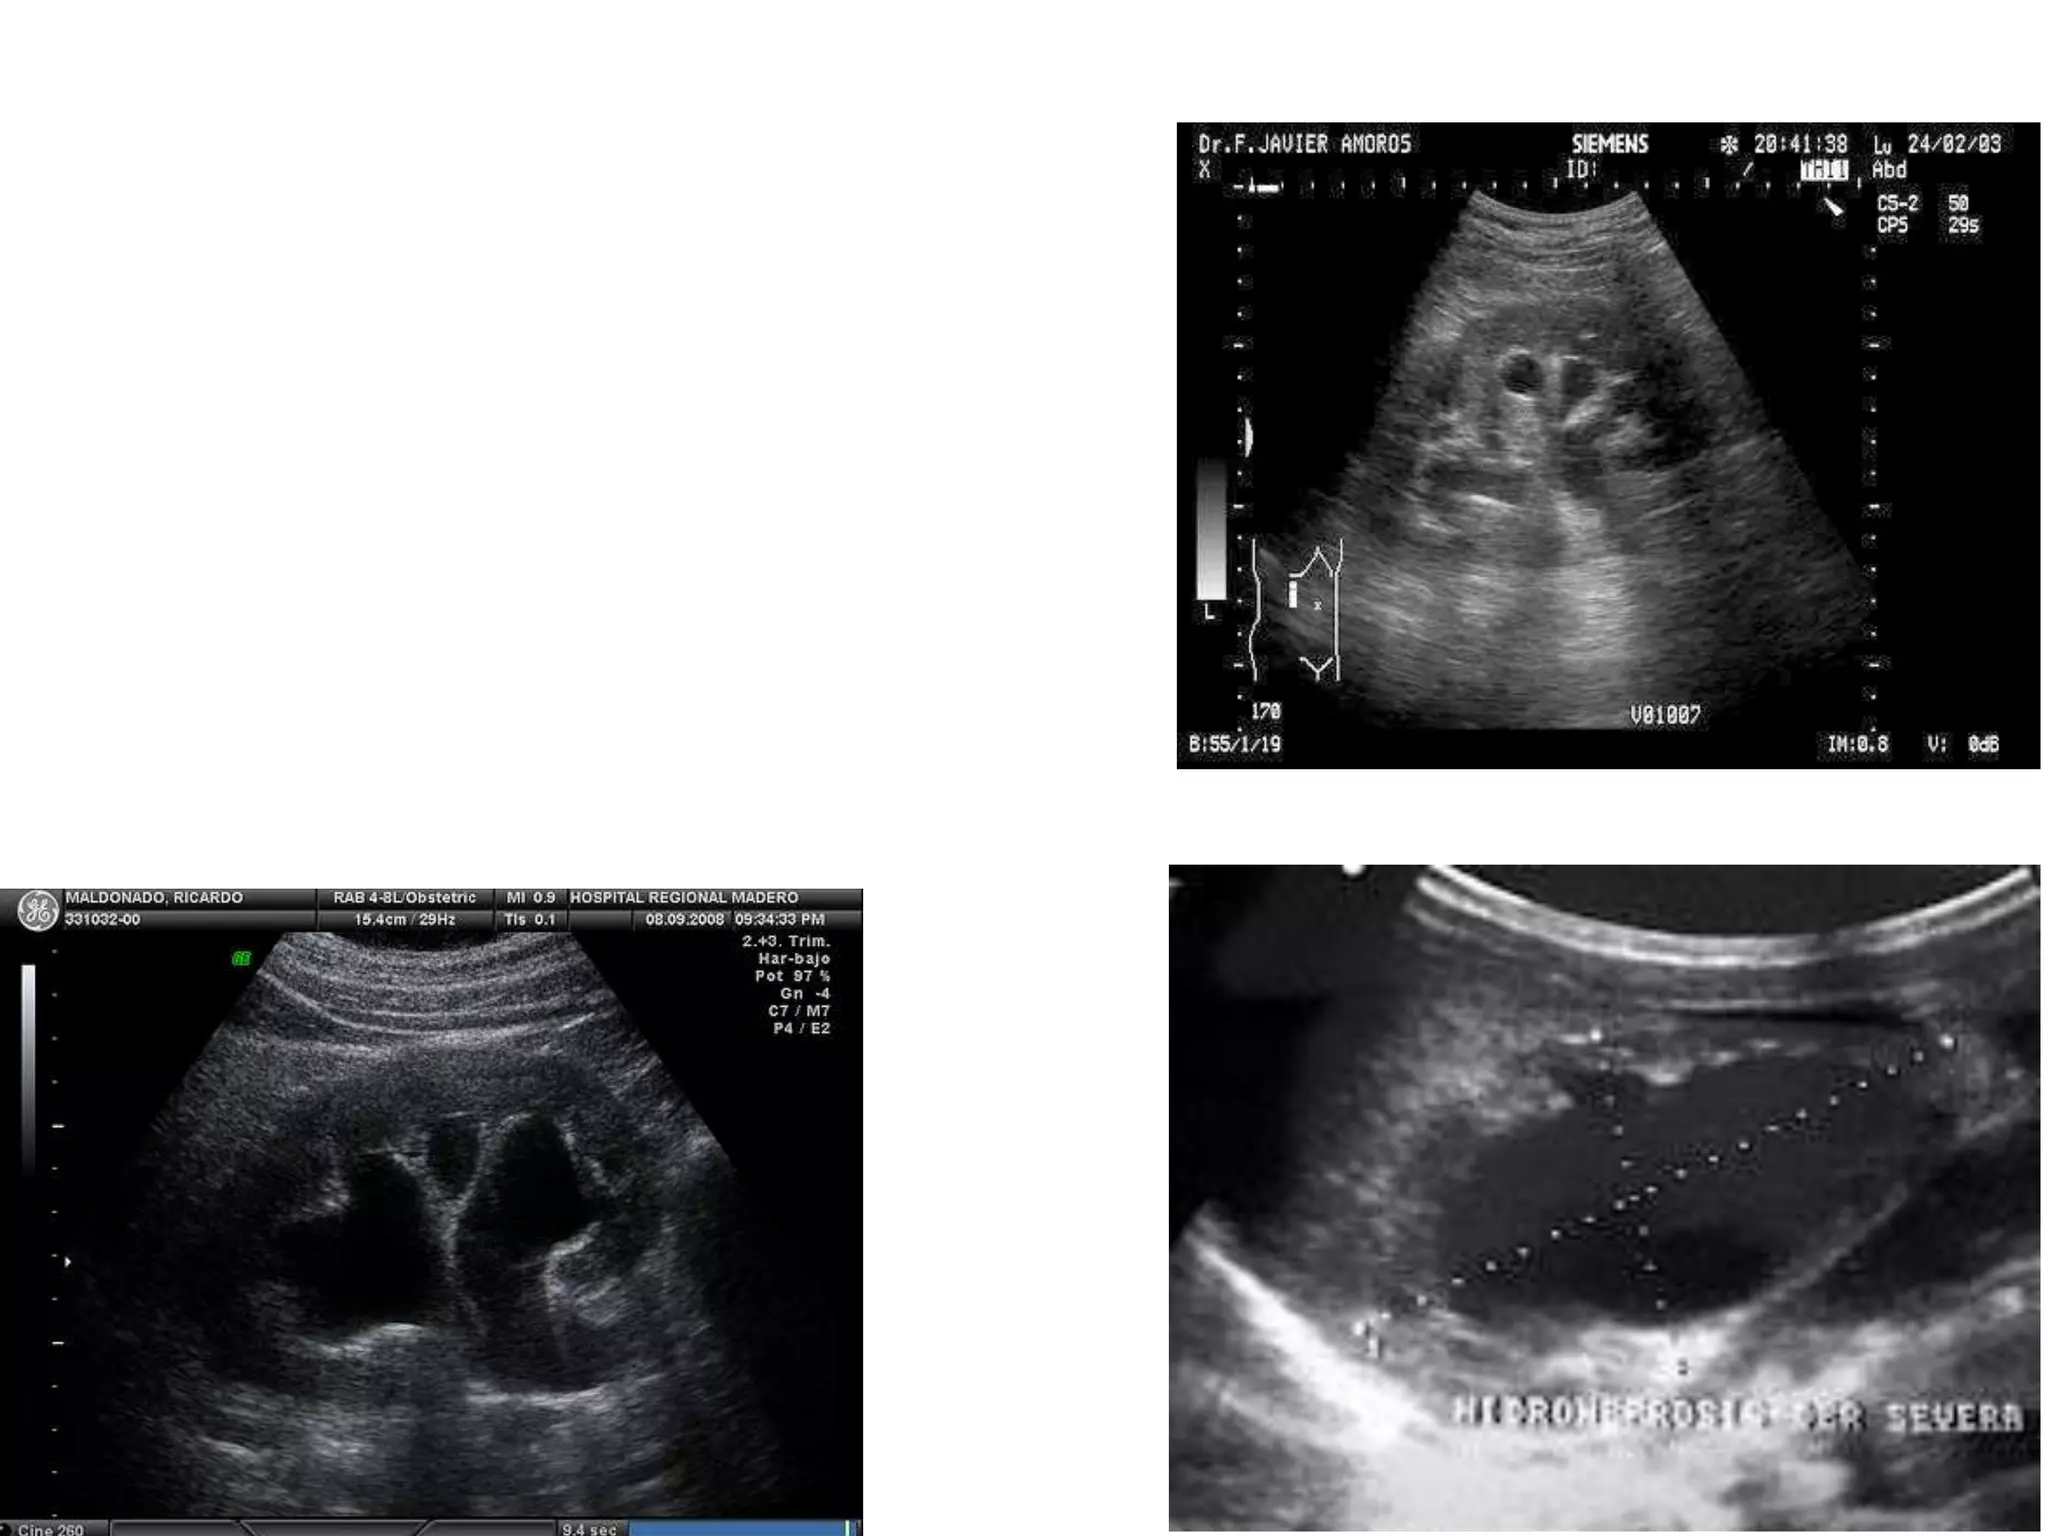

Mejor prueba de imagen

Ultrasonido para diagnostico inicial

TC+C para la resolucion de problemas

Caracteristicas generales Dilatacion pielocalicial Dilatacionutereral. Mejor prueba de imagen Ultrasonido para diagnostico inicial TC+C para la resolucion de problemas